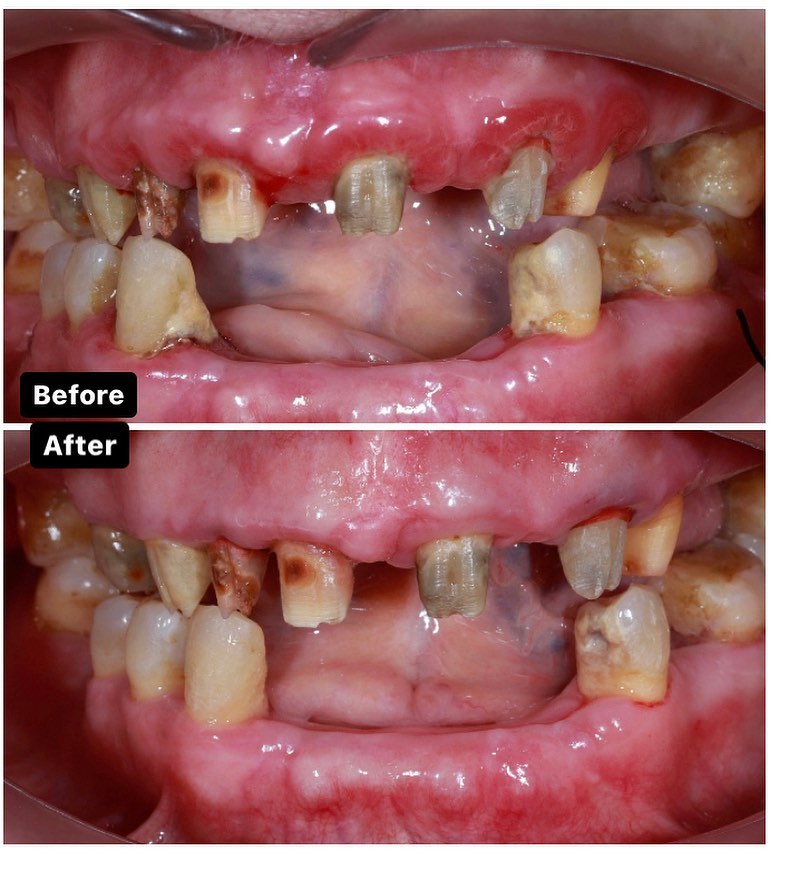

Diş ətinin iltihabı

Diş ətində olan qızartı, şişkinlik və qanama kimi əlamətləri olan diş əti xəstəlikləri müalicə olunmalı və sonra qapaq ilə implant edilməlidi